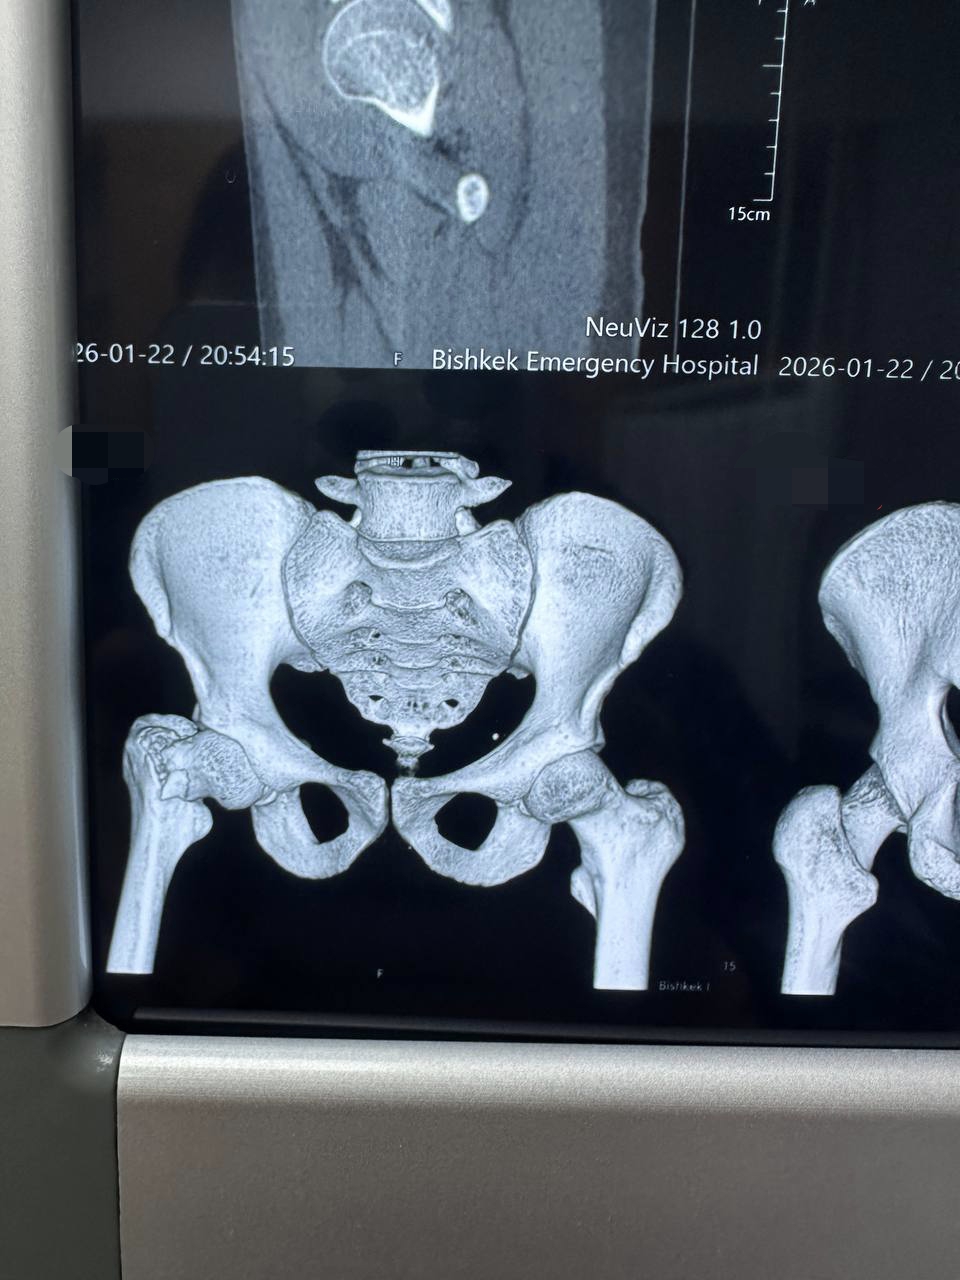

Всех приветствую. Недавно моя жизнь круто изменилась. Я получил тяжелую травму.

Диагноз: Субкапитальный перелом шейки бедра со смещением и укорочением 5 см.

Уже перенес операцию. Еще долго буду лежать в больнице.Шансы что смогу ходить есть. Восстановление при благоприятном исходе займет 8 месяцев в лучшем случае.

Тяжелые боли,время и финансовые расходы.

И я прошу помощи на восстановление.

Боюсь деньги не сильно повышат шансы. Но лечение, препараты все стоит денег...

Прошу помощи в размере 30к.

Даже любая копейка может хоть немного снизить финансовую нагрузку)

Всем крепкого здоровья ибо только потеряв его начинаешь по настоящему его ценить